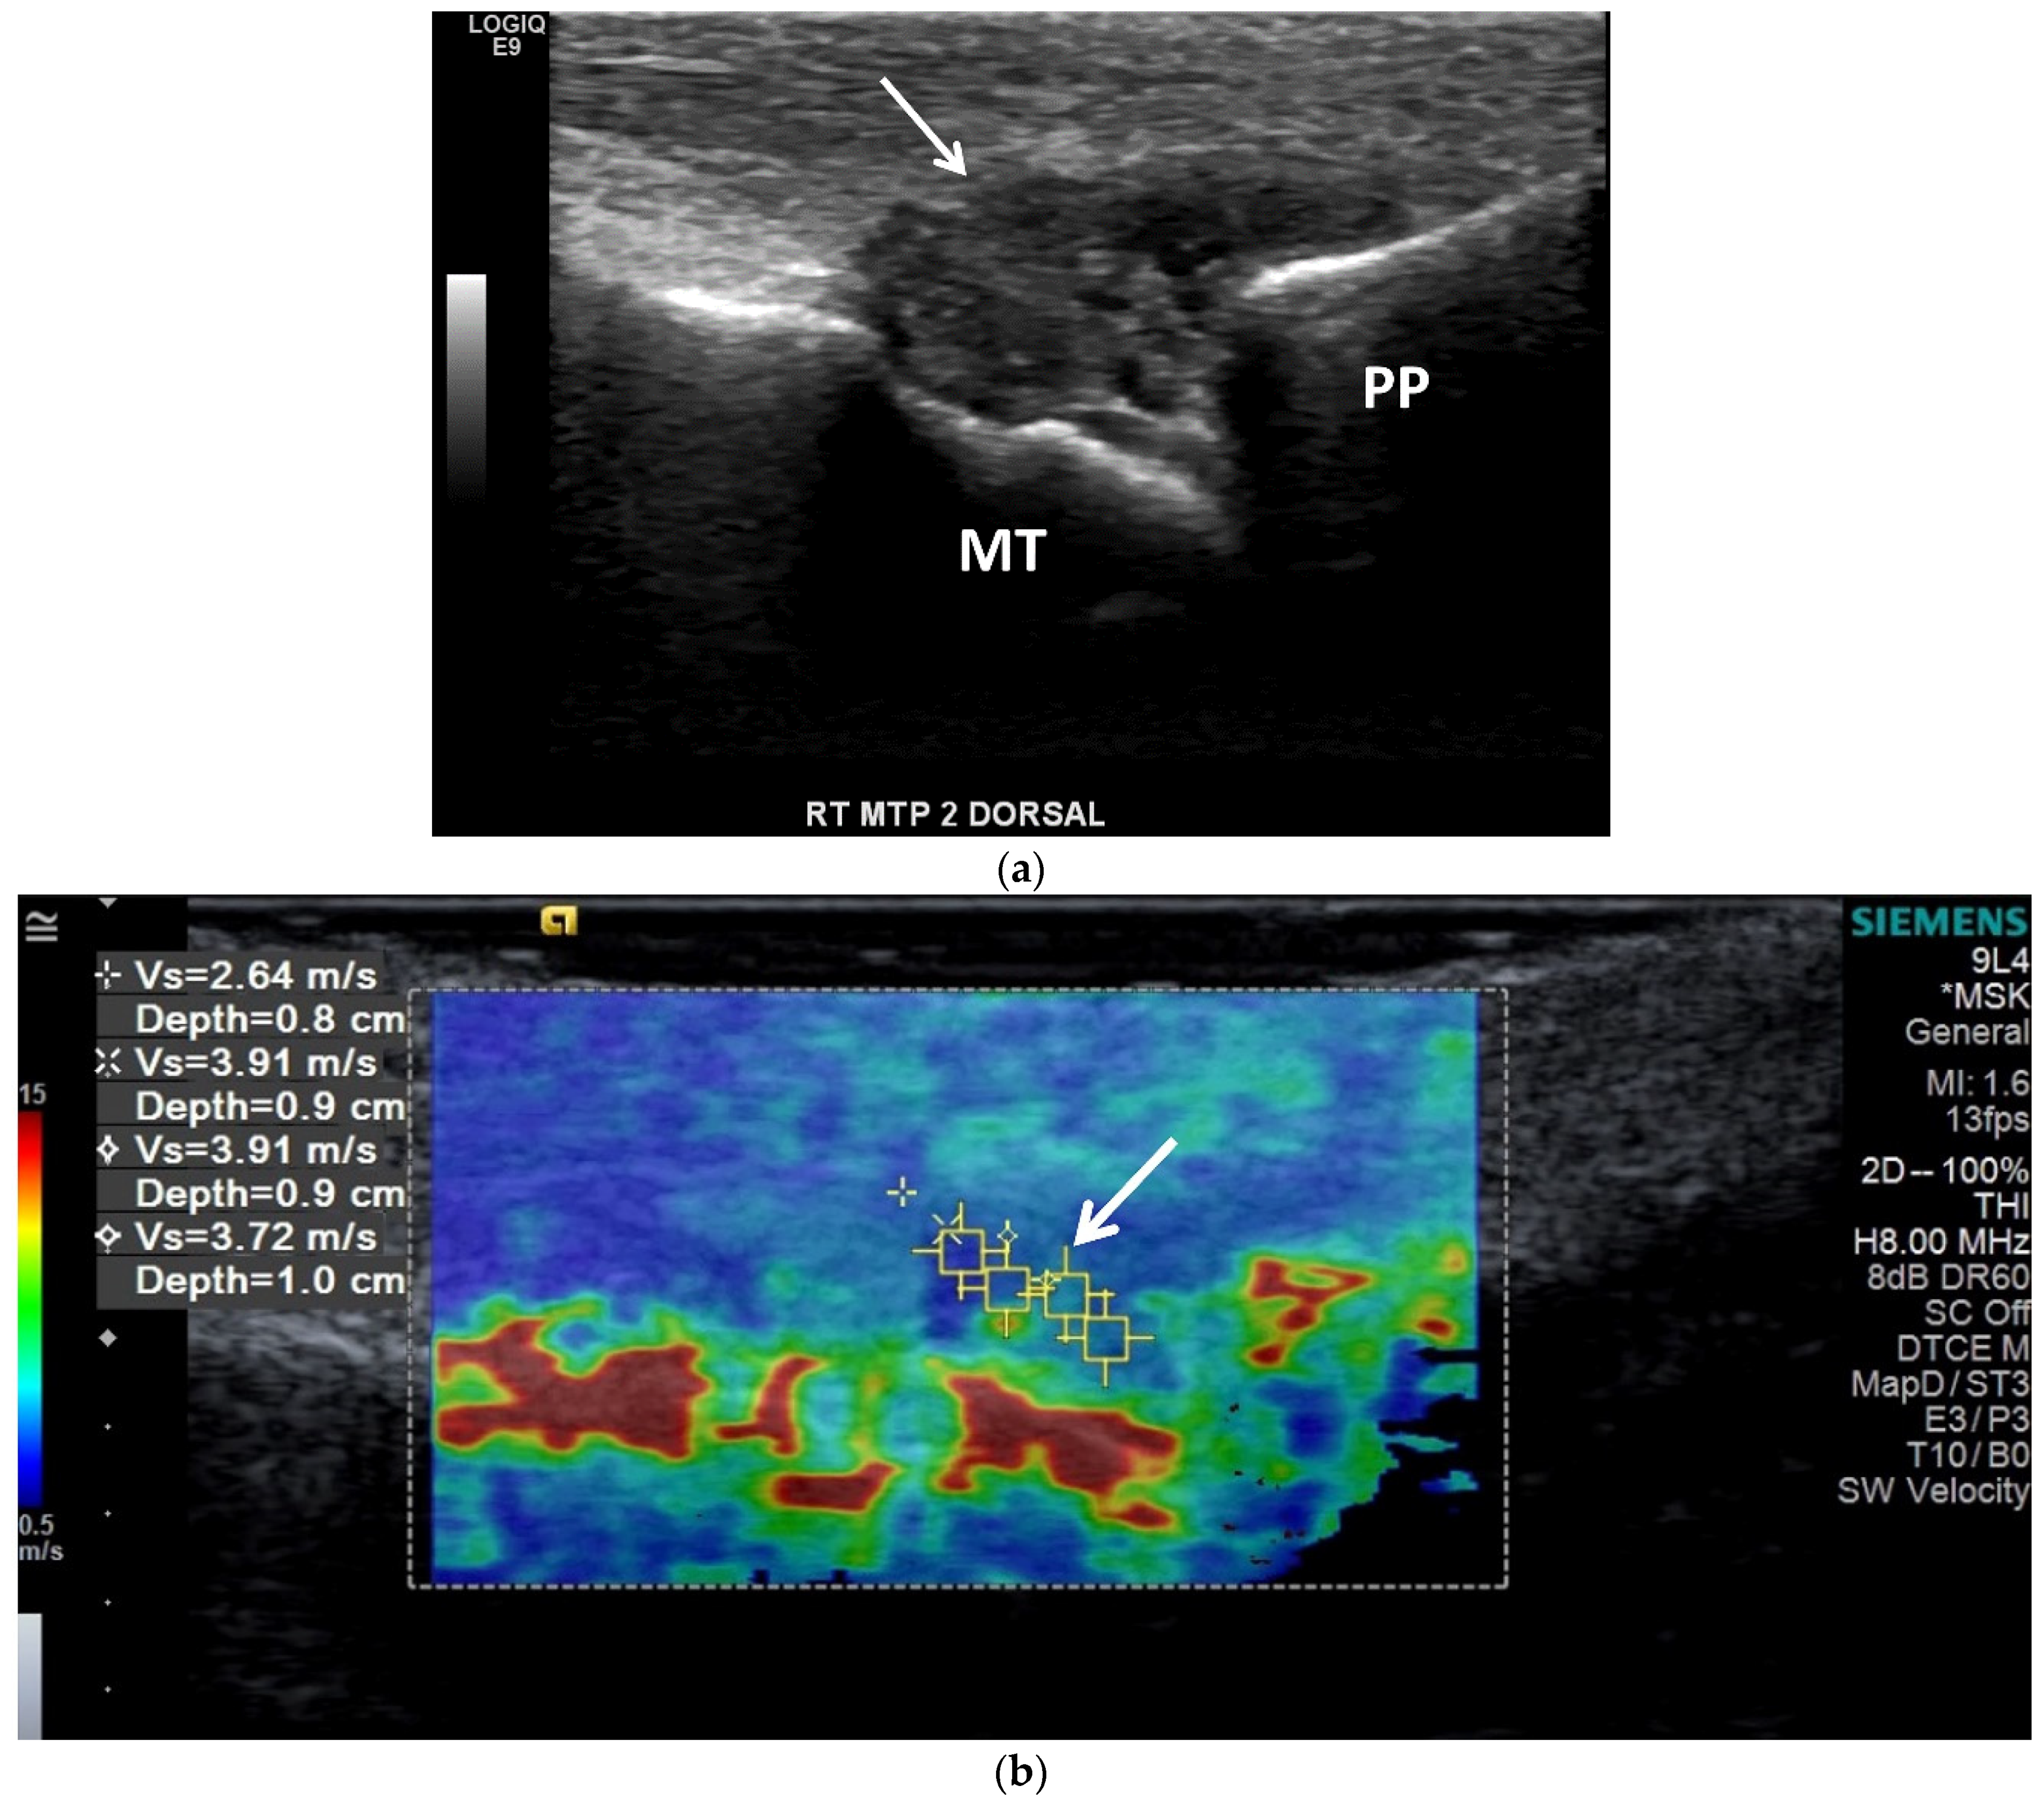

3.2. Ultrasound (US)

3.3. Computed Tomography (CT): Conventional and Dual Energy (DECT)